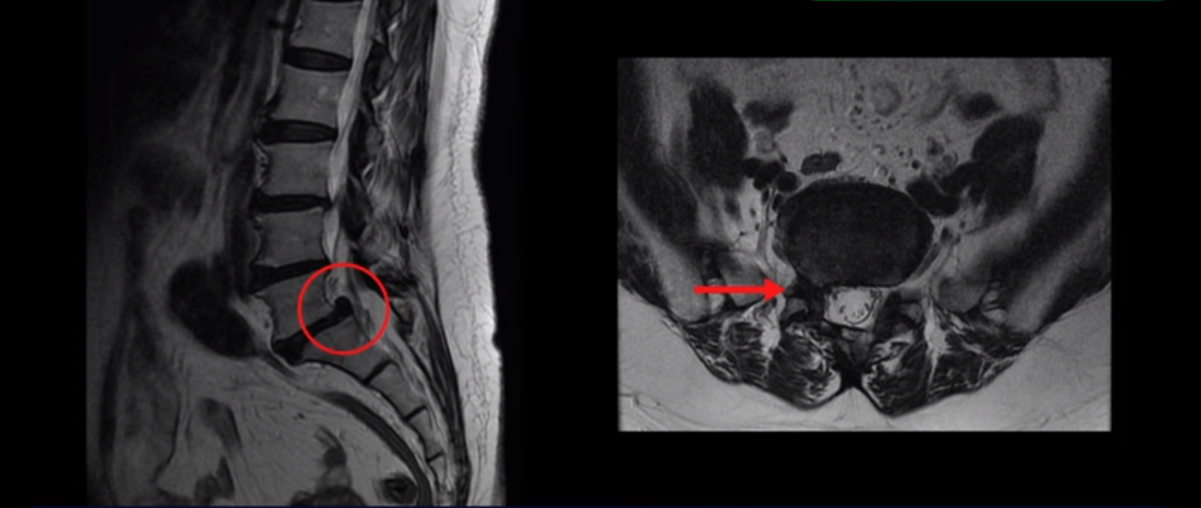

이 환자분은 허리통증과 오른쪽 엉치통증, 그리고 다리에 방사통이 있는 환자분이었습니다.

MRI를 보면 5번과 1번에 전방전위증과 척추분리증, 그리고 오른쪽으로 신경이 나가는 추간공을 막고 있는 디스크 탈출과 추간공협착증이 있습니다. 보시다시피 디스크와 뼈로 인해 신경이 나가는 구멍이 막혀 있습니다.